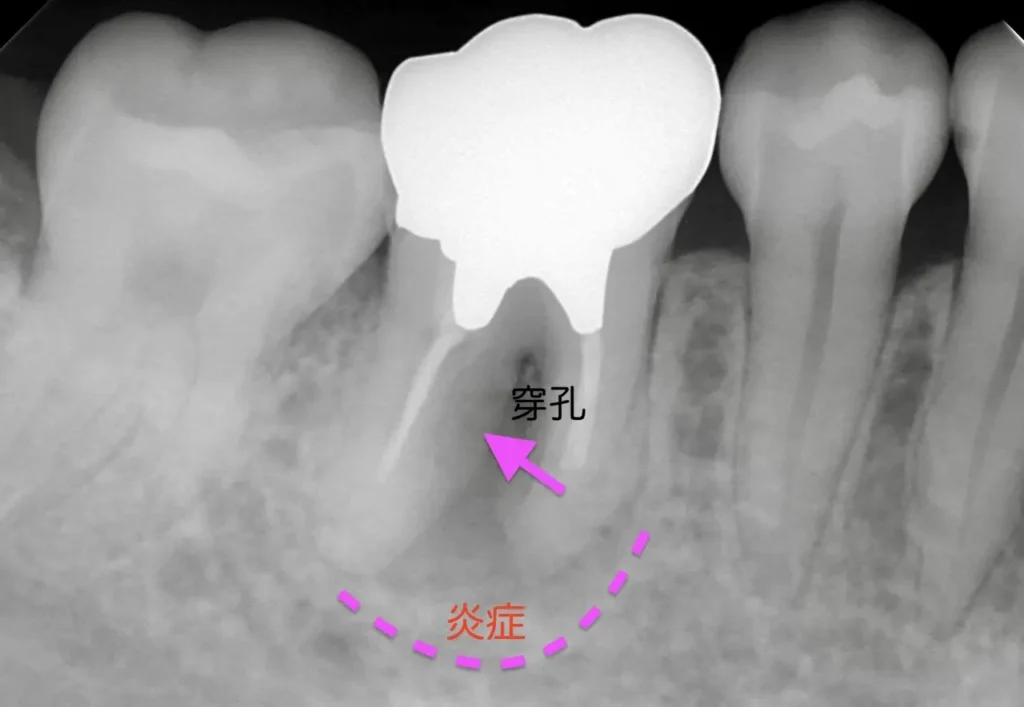

自費根管治療症例7 治療前(感染根管処置、穿孔封鎖)

「銀歯がひどく痛む」

初診時

前医の治療の時に根管に孔が空いたようです

むし歯除去後の写真

管の途中に孔が確認できます

術前

銀歯です